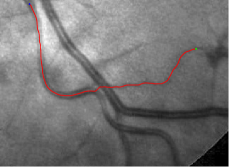

In this paper, we propose a coherence-penalized minimal path model, where the associated minimal paths favour to pass by a vessel that is located in the flatten region of an external feature map. We observe that along a piece of retinal vessel, the values of gray levels vary slowly. More specifically, retinal arteries have lower contrast of gray levels than veins due to the blood materials and imaging modality. In other words, in some extent the arteries and veins are distinguishable in terms of vesselness values. Such an observation can be used to solve the short branches problem that the minimal paths associated to a metric may pass through segments belonging to different vessels as shown in Figs. 1b and 1c. Fig. 1d shows the result from the proposed method, which can avoid such problem. Fig. 1a gives the artery-vein (AV) groundtruth. In this paper, we denote by blue and green dots the source and end points respectively.

Validation. We validate our minimal path model on respective 54 and 30 patches obtained from the DRIVE [14, 15] and the IOSTAR [16] datasets with AV groundtruth. Each artery involved in these parches locates near a vein or crossing it at least once. Our goal is to extract the artery between two given points. In order to get the quantitative evaluation, we first convert each continuous spatial path to an 4-connected digital path which is considered as a pixel collection. We denote by the collection of digital path pixels inside the artery groundtruth map . Thus, a measure can be simply defined as , where and mean the respective number of elements involved in and . We compare our model to four existing minimal path models: the isotropic Riemannian (IR) model [1], the anisotropic radius-lifted Riemannian (ArR) model [4], the isotropic orientation-lifted Riemannian (IoR) model [5] and the curvature-penalized (CuP) model [7]. The construction of these metrics are based on the OOF outputs [12]. Note that a centerline-based potential is chosen so that we remove the radius dimension of [5] to reduce computation complexity. The results in terms of the score are presented in Table 1, including the average (Avg.), maximum (Max.), minimum (Min.) and standard deviation (Std.) values. In both DRIVE and IOSTAR datasets, our method can achieve the best performances thanks to the coherence penalization. Note that in Table 1, we evaluate our method by using the refined paths instead of using the original coherence-penalized minimal paths. For comparisons in visualization, we show the minimal paths from the ArR metric , the CuP metric and the proposed coherence-penalized metric on three retinal patches as shown in Fig. 3. The targeted artery vessels which cross veins at least once are labeled by red color in column 1. The paths shown in column 4 from the proposed metric are results after refinement. One can claim that our method indeed can catch expected arteries while other metrics fall into the traps of short branches combination.